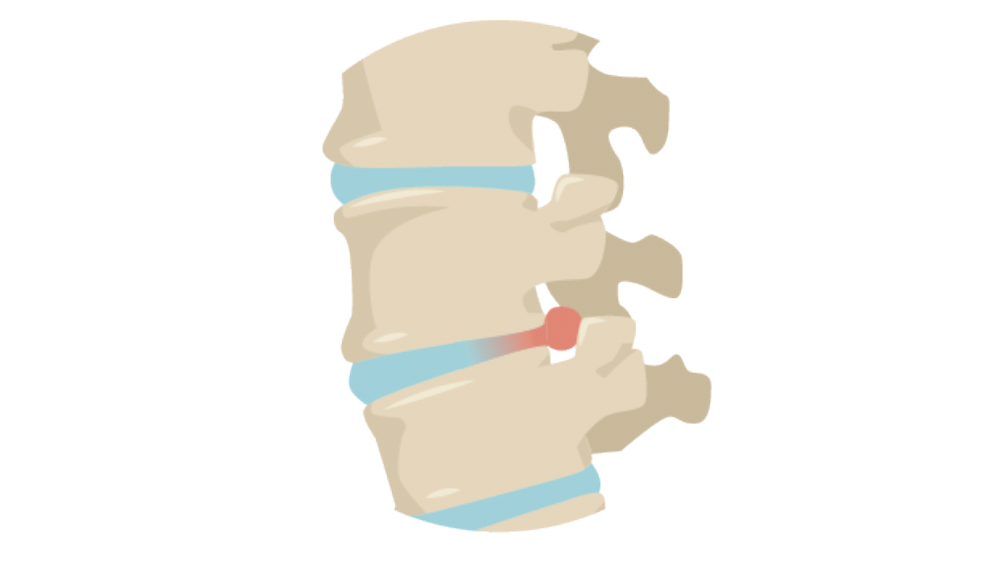

L’ostéopathie est une pratique thérapeutique douce, à la fois curative et préventive. Elle a fait ses preuves dans le traitement des troubles musculo-squelettiques (TMS) et le stress qui constituent un problème de santé au travail et ont causé 8 millions de jours d’arrêt de travail en France en 2018. Faire intervenir un ostéopathe en entreprise est donc un choix judicieux pour maintenir les salariés en bonne santé et donc en bon état de productivité. L’ostéopathe peut prévenir et traiter les TMS les plus fréquents, que sont les tendinopathies, les lombalgies chroniques, les cervicalgies ou encore le syndrome du canal carpien par l’ostéopathie, assure le bien-être du personnel au travail.

Reconnue pour son efficacité contre les maux du dos, l’ostéopathie est capable de soulager les affections et les troubles du système musculo-squelettique.

Il s’agit des problèmes aigus comme les entorses, les blessures sportives ou chroniques comme les hernies discales, les lombalgies, les douleurs articulaires, les douleurs périnatales, les scolioses et les tendinites. Elle est également efficace contre la fasciste plantaire, le syndrome du canal carpien, l’épine de Lenoir et les troubles musculo-squelettiques (TMS) causés par les postures de travail (travail prolongé à l’ordinateur par exemple).